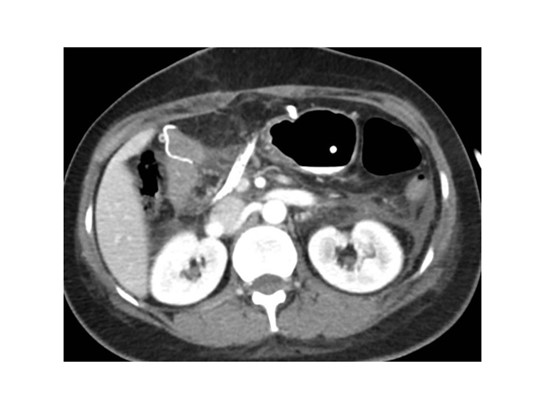

Paciente femenina de 50 años de edad con antecedentes de HTA. Anexo histerectomía total por carcinoma de útero, apendicetomía, colecistectomía, cesárea, resección de tumor basocelular. Derivada de Hospital Regional Dr. Luis Pasteur de Villa María de Córdoba el 21 de marzo de 2021 a Hospital Sanatorio Franchin por cuadro de hipoglicemias severas sintomáticas a repetición, con laboratorios clínicos donde se observó hipoglicemia asociada a hiperinsulinismo; el péptido C se encontraba elevado. Se realizó imágenes (TAC, RMN) que evidenciaban lesión en región de cabeza de páncreas medial con refuerzo arterial, compatibles en primera instancia con insulinoma. Se decide conducta quirúrgica debido a clínica, realizándose el día 27 de abril de 2021 duodeno pancreatectomía, evolucionó con fístula pancreática con requerimiento de octreotide. Posteriormente se realizó seguimiento de la paciente sin evidencia de síntomas de hiperinsulinismo, y en los controles radiológicos no se encontró recurrencia.

Paciente femenina de 48 años de edad que ingresa a Hospital Sanatorio Franchin por síntomas de cefalea y mareos, cuadro que se hace progresivo, presentando síncopes y posteriormente alteración del estado de conciencia. Los exámenes clínicos revelan una glucosa de 40 mg/dl, concomitante con insulina alta y péptido C elevado. Ingresa de forma programada para realización de duodeno pancreatectomía el 29 de mayo de 2021. Imágenes diagnósticas muestran estudio trifásico de tomografía de abdomen, lesión nodular en la cabeza del páncreas con ávido realce en fase arterial que en resonancia magnética se observa hiperintensa en T2, presenta restricción con la difusión y caída de la señal en el ADC. Además presenta realce tras la administración de contraste con gadolinio.